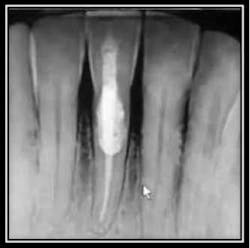

Radiographic Resorption:

Perioscopic view of external root resorption #15.Suggested Etiology: Impacted 3rd molar The below case identifies external root resorption which extends into the cementum and dentinal structures.

Pre-op radiograph #15

The above pictures identify the resorption. The interior of the resorption is quite hard and may be Reparative dentin, which is formed as a reaction to external stimulation.

Treatment for this type of defect may vary depending upon the extent of the resorption.